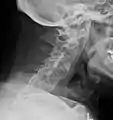

X-rays

The earliest changes demonstrable by plain X-ray shows erosions and sclerosis in sacroiliac joints. Progression of the erosions leads to widening of the joint space and bony sclerosis. X-ray spine can reveal squaring of vertebrae with bony spur formation called syndesmophyte. This causes the bamboo spine appearance. A drawback of X-ray diagnosis is the signs and symptoms of AS have usually been established as long as 7–10 years prior to X-ray-evident changes occurring on a plain film X-ray, which means a delay of as long as 10 years before adequate therapies can be introduced.[24]

Lateral X-ray of the neck in ankylosing spondylitis